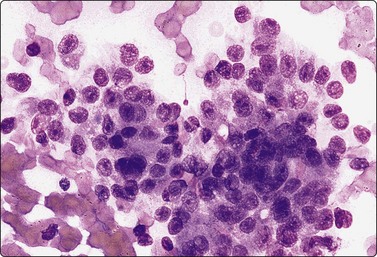

Nasopharyngeal carcinoma (NPC) (Figs 4.8, 4.9, and 5.59)44-47

image

Fig. 4.8 Nasopharyngeal carcinoma (squamous cell carcinoma, WHO type II)

Epithelial fragment of spindly and basaloid squamous epithelial cells with no evidence of keratinization (Pap, HP).

Nasopharyngeal carcinoma (NPC) is a clinicopathologic entity different from other squamous cell carcinomata of the head and neck. It is distinguished by its particular histology, geographic distribution, relationship to Epstein-Barr virus, and the absence of an alcohol or tobacco etiological relationship. A proportion of NPCs show squamous differentiation and the cytological pattern of non-keratinizing squamous cell carcinoma (squamous cell carcinoma/WHO type II) (Fig. 4.8). Keratinized cells (WHO type I) are uncommonly found. The majority of NPC are poorly differentiated or undifferentiated. Cells from undifferentiated NPC (UCNT, WHO type III) form loose clusters with no specific microarchitectural pattern, and are usually mixed with lymphoid cells. In the ‘lymphoepitheliomatous’ type (Schmincke-Regaud) the cells tend to be less cohesive, resembling Hodgkin’s disease or large cell non-Hodgkin lymphoma. However, in NPC, the malignant cells are still clustered and have more abundant pale cytoplasm contrasting with the lymphoid cells in the background (Fig. 4.9). Plasma cells are frequently found among the lymphoid cells. Immunostaining for cytokeratin and a pan-lymphocyte marker is helpful. Epstein-Barr virus-associated nuclear antigen is demonstrable by anticomplement immunofluorescence in undifferentiated tumors. Other patterns of growth may occur and may cause diagnostic problems; for example, spindle cell forms may be difficult to recognize as carcinoma.

NPC frequently presents to the cytologist as a lymph node metastasis in the neck without a known primary. Cytological recognition is important since the primary is often clinically occult.